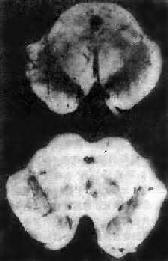

黑质和蓝斑脱色是本病肉眼变化的特点(图16-35)。镜下可见该处的黑色素细胞丧失,残留的神经细胞中有Lewy小体形成,该小体位于胞浆内,呈圆形,中心嗜酸性着色,折光性强,边缘着色浅。电镜下,该小体由细丝构成,中心细丝包捆致密,周围则较松散。

图16-35 Parkinson病

中脑黑质脱色(下),正常中脑黑质完好(上)